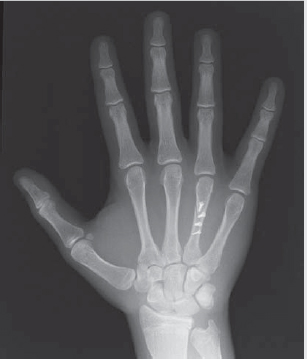

Usually, a full hand X-ray series suffices to diagnose all metacarpal fractures.